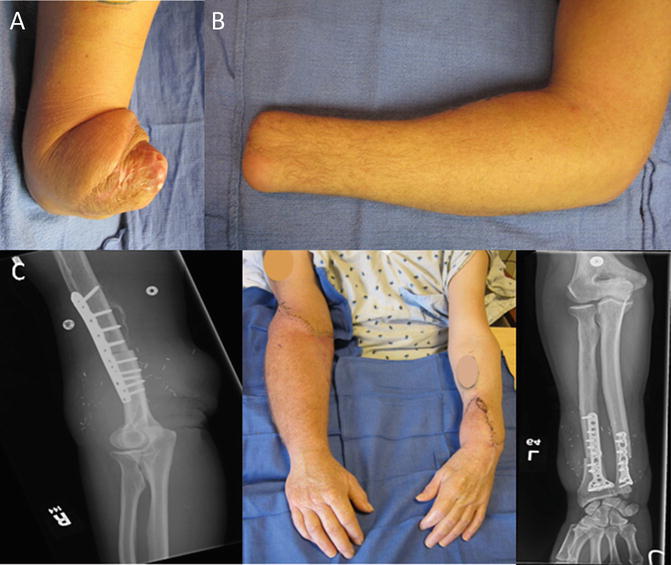

Leg ulcers that do not heal despite appropriate treatment are defined as recalcitrant ulcers. A bone transplant may also be performed using bone tissue from a cadaver. In order to perform the graft your surgeon may take bone from your hips legs or ribs.

After sharp debridement dermal substitutes including skin from cadaver donors may increase the healing rate of recalcitrant ulcers. Autograft is a decision that must be made by the surgeon and patient said co-author Kurre Luber MD orthopedic surgery fellow at Mississippi Sports Medicine and Orthopaedic Center. Risks From Cadaver Tissue Are Exceedingly Low We know that the chance of developing an infection as a result of disease transmission from an allograft implanted is exceedingly low.